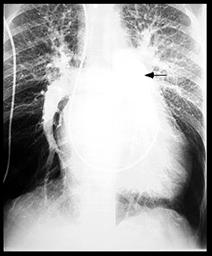

3. VD + AD - sunt mai mult sau mai putin dilatate in functie de gradul HTP: VD dilatat sau hipertrofiat, infundibulul pulmonar dilatat (Rx bombarea arc.II stg.), AD dilatat, 10% din cazurile de SM se pot asocia cu leziuni tricuspidiene.

3. Rx. poate arata:

o silueta cardiaca mitrala,

largirea AS (PA, OAS, LS),

dublu contur dr.,

calcificari mitrale sau de AS,

VS mare sau mic,

semne de hipertensiune veno-capilara:

redistributie venoasa lobara sup,

edem interstitial,

linii Kerley exprima staza limfatica (A-la hil, B-la baza SM stransa, C-intre),

edem alveolar,

epansament pleural.

hemosideroza,

calcificari

pulmonare,

infarct pulmonar,

alte boli pulmonare

asociate.